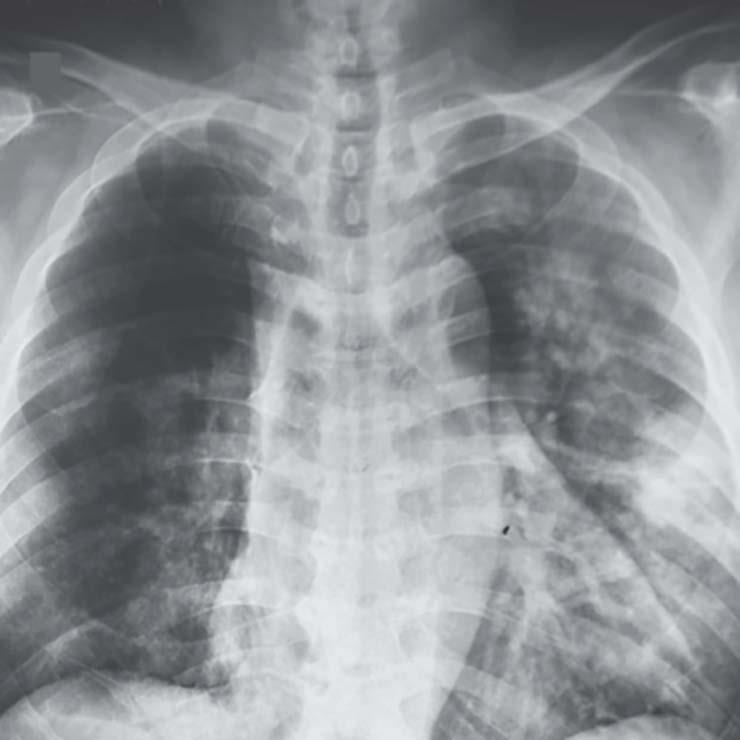

ووفق بيانات اللجنة الوطنية للصحة بالصين، فإن 80 بالمائة من المُتوفين جراء "كوفيد 19" كانوا فوق الـ 60 عامًا، و75 بالمائة منهم عانوا من أمراض مزمنة مثل أمراض القلب والأوعية الدموية والسُكري. ويسبب التهابات حادة في الجهاز التنفسي، عادة ما تبدأ أعراضها بحُمى ثم سعال جاف.

يأتي ذلك في ظل طريقة جديدة باتت السلطات الصينية تعتمدها لاحتساب عدد الإصابات منذ 3 أيام، تتمثل في إضافة الحالات "المُشخّصة سريرًا" التي يُكتشف إصابتها بالتصوير الإشعاعي للرئتين دون الحاجة إلى إجراء فحص الحمض النووي، وذلك بهدف تسهيل العلاج المُبكر للمُشتبه في إصابتهم بالعدوى.